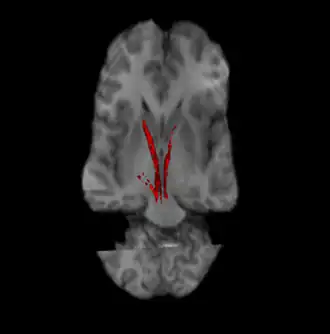

Nigrostriatal pathway (Left and Right in red). | |